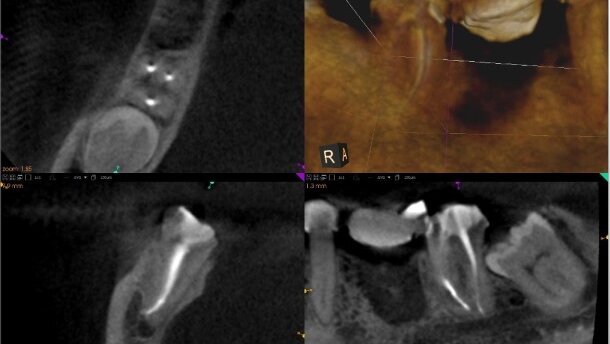

Ze względu na obraz radiologiczny pokazujący dużą odległość wypełnienia od wierzchołków radiologicznych, pacjentkę skierowano na badanie tomograficzne. Po wykonaniu badania i jego analizie, wszelkie wątpliwości zostały rozwiane (Ryc. 4 i 5). Nietypowe ułożenie wierzchołków anatomicznych zęba 47 sprawiło, że klasyczne zdjęcie rvg wprowadzało operatora w błąd, sugerując niedopełnienie. Uzyskanie przekrojów czołowych pozwoliło prawidłowo zobrazować anatomię i jakość wypełnienia w przedstawionym leczeniu.